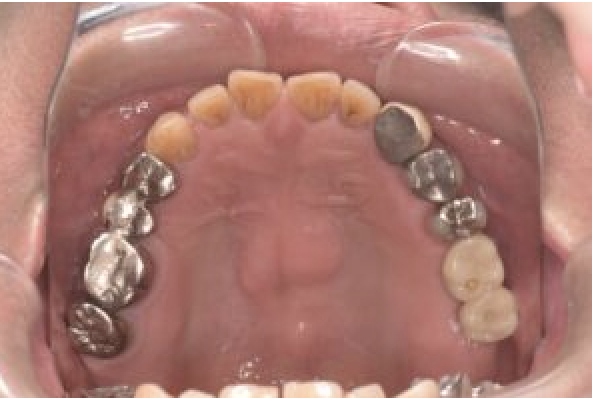

| 備考 | 右上の欠損部へのインプラントを希望で来院されました。 左下のブリッジの下にものが挟まりやすいとのことでブリッジ部分もインプラント埋入を希望されました。口腔内の銀歯も全て綺麗にやりかえたいとのことで、ダイレクトボンディングやセラミックインレーやジルコニアクラウンでやりかえていきました。 右上6番のインプラント埋入時にはソケットリフトで骨造成を行なっています。 見た目だけではなく噛みやすくなりとても満足されています。現在はエアフローのクリーニングやホワイトニングで通院されています。 |